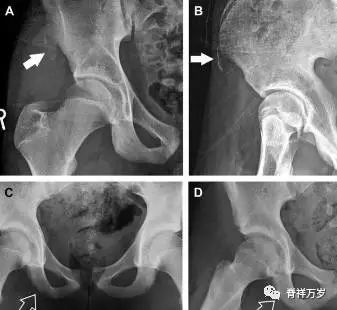

儿童撕脱性骨折

撕脱性骨折常在体育运动时由于肌肉强烈收缩引起。图 3 为容易发生儿童撕脱性骨折的部位。

图 4 儿童撕脱性骨折。正位片(A)和斜位片(B)示从髂前上棘撕脱的骨折碎片(箭头)。正位片(C)和另一个患者的蛙式位片(D)示右侧坐骨支皮质毛糙,腘绳肌腱撕脱损伤(如 C 和 D 空箭头所示)